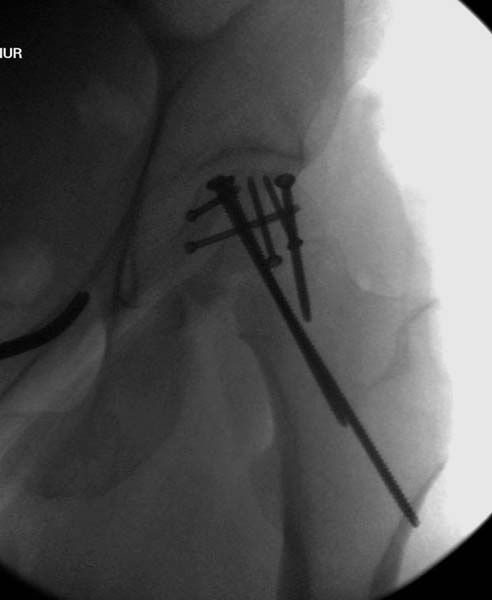

Больная стабильная после хирургических мероприятии и получив добро, приступили к закрытому вправлению таранной кости с укладкой наружного фиксатора. Затем укладка больную на бок и открытый остеосинтез перелома-вывиха головки бедра.

По характеру повреждения головка находится сзади и напрашивается задний Кохер-Лангенбек доступ, но в заднем доступе имеется риск повреждения магистрального кровоснабжения головки a. circumflexa. Более щадящая trochanteric flip (digastric osteotomy) сохранит кровоснабжение и дасть возможность работу при вывихнутом суставе.

После спадения отека на стопе произведена фиксация тарана. Кстати, коллеги пересмотрели первоначальную консультацию по позвоночнику и на двух уровнях провели фиксацию. Из-за длительного постельного режима без нагрузки таз не стали оперировать...